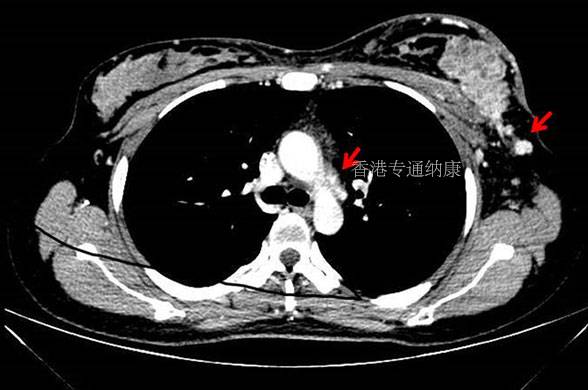

HER2也是非小细胞肺癌中较为常见的一个突变,发生率在2%~4%左右。与乳腺癌中不同,肺癌的HER2突变以20外显子的插入突变HER2YVMA为主,这也使得现有的HER2靶向疗法在肺癌中疗效不佳,无一获批。

而DS-8201改变了这一切。在DESTINY-Lung01研究中,接受DS-8201治疗的91位HER2阳性非小细胞肺癌患者,1人完全缓解,49人部分缓解,共有84人的肿瘤缩小,客观缓解率和疾病控制率分别达到了55%和92%。

随后的DESTINY-Lung02研究中,DS-8201又在目前的52名HER2阳性肺癌患者中,取得了58%的客观缓解率和8.7个月的中位疗效持续时间。

FDA也因此加速批准了DS-8201用于接受过全身治疗的HER2阳性不可切除或转移性非小细胞肺癌,让它成为了首个用于肺癌的HER2靶向疗法。